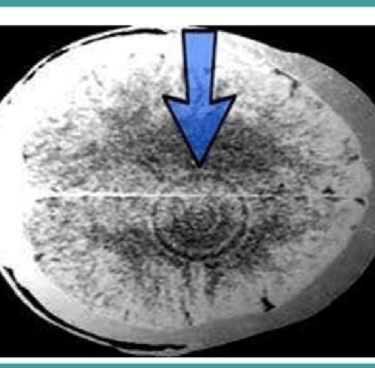

Para validar a relação entre o trauma e a manifestação física da doença, Hamer utilizou tomografias cerebrais para identificar o que ficou conhecido como “Focos de Hamer” — áreas específicas no cérebro que apresentavam alterações estruturais visíveis após o paciente ter vivido um choque emocional intenso. Essas imagens mostravam anéis concêntricos, semelhantes a alvos, que, segundo ele, indicavam a conexão direta entre o trauma psíquico e a ativação de determinadas áreas cerebrais. Cada um desses focos correspondia a uma área do corpo onde os sintomas se manifestavam.

Por exemplo, em pacientes com câncer de mama, Hamer frequentemente identificava um foco no tronco cerebral, região associada ao controle das glândulas mamárias. Em pacientes com câncer de pulmão, os focos eram observados no mesencéfalo, sugerindo uma relação entre conflitos de medo da morte e o desenvolvimento da doença nos pulmões.

Foco de Hamer